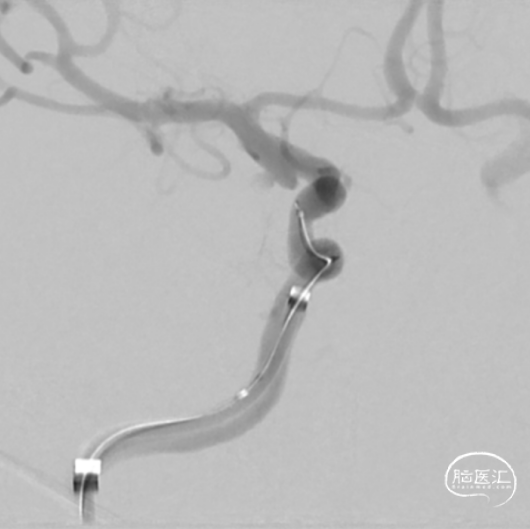

穿刺右股动脉,造影证实右侧后交通动脉瘤,微小宽颈动脉瘤,5F多功能造影管带通桥银蛇6F-115直奔主题,进入右侧颈内动脉,路径图指引下微导管引导支架微导管到达预定位置,然后通过微导丝引导栓塞导管进入瘤腔,分别依次填入3D2*4cm、1.5*2cm、1*1cm三枚弹簧圈,栓塞结束后造影显示动脉瘤致密栓塞,依次撤出器械,结束手术。

工作位造影

银蛇到位

支架微导管到位

栓塞微导管到位

栓塞第一枚弹簧圈

栓塞第二枚弹簧圈

栓塞结束后造影